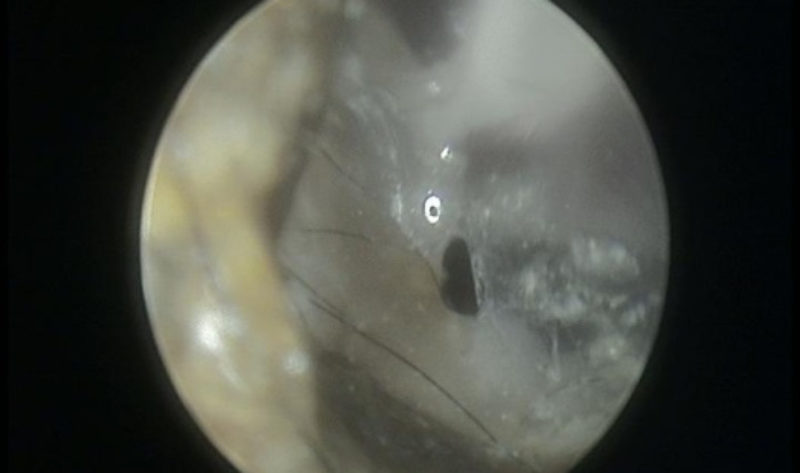

Weiter wurde Leo in tiefer Inhalationsnarkose untersucht. Während eine Assistentin Leos Narkose überwachte, konnten wir mit dem Videootoskop (Ohrenuntersuchung mit stark vergrößertem Bild auf einem Bildschirm) die Ohren genau betrachten. Zuerst musste dafür der ganze Ausfluss gründlich herausgespült werden. Die gesamte Gehörgangshaut beider Ohren war stark gerötet und den Ausfluss zu entfernen, brauchte etwas Zeit. Solange das Trommelfell (die Trennmembran zwischen äußeren Gehörgang und Mittelohr) nicht sicher gesehen werden kann, muss sehr vorsichtig vorgegangen werden, weil eben in das Mittelohr kein normaler Ohrenreiniger gelangen darf. Während in Leos rechtem Gehörgang nach der Ohrspülung ein reizloses gesundes Trommelfell zu sehen war, zeigte das linke Trommelfell in der Videootoskopie deutlich eine Trübung und ein Loch. Das sind sichere Hinweise auf eine Mittelohrentzündung. Leo hatte uns schon bei der klinischen Untersuchung einen Hinweis gegeben: der trockene rissige Nasenspiegel aufgrund der Reizung eines durch das Mittelohr laufenden Nerves. Nun wurden in Narkose Röntgenbilder von den Ohren (besonders wichtig waren hier die Mittelohren) angefertigt und direkt ausgewertet. Leos Paukenhöhle (das Mittelohr) zeigte noch keine Veränderung im Knochen. Also wurde nun direkt der ganze Eiter aus dem linken Mittelohr sehr vorsichtig mit verträglichen Flüssigkeiten über einen dünnen Schlauch herausgespült und die erste Probe auch wieder unter dem Mikroskop untersucht. Wieder waren Bakterien und Entzündungszellen zu sehen. Um Leo sofort helfen zu können, wurden Medikamente direkt in die Paukenhöhle eingebracht, um dort über mehrere Tage ihre Wirkung zu bringen. Mit einem Schmerzmittel versorgt durfte Leo wach werden.